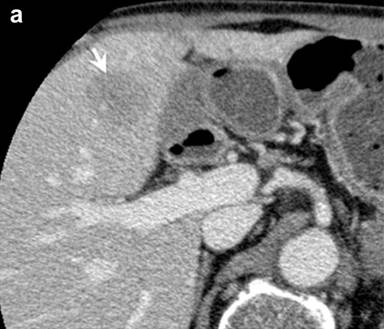

Following the diagnosis of autoimmune pancreatitis, screening CT images demonstrated pelvic lymph nodes that gradually increased in size (about 1.5 cm) and number. In June 2009, following CT detected an ill-enhanced hepatic tumor (Figure 3a). Endoscopic examinations denied upper and lower gastrointestinal tumors that could be the origin of hepatic tumor. Various candidates were considered, such as pseudotumor, cholangiocarcinoma, hepatocellular carcinoma, hepatic adenoma and metastasis of past bladder cancer. Percutaneous needle biopsy was performed to reach a final diagnosis. Histology of the biopsy tissue was urothelial carcinoma (Figure 3b), the same as in the bladder resected 5 years and 6 months previously (Figure 3c). The patient refused a second operation. Chemotherapy with gemcitabine was initially effective, but failed in one year, and metastasis developed in the adrenal gland, paranasal sinuses, and cervical vertebrae. Second line therapy by paclitaxel was not effective and the patient succumbed in January 2011.

Figure 3. Hepatic metastasis of the bladder cancer. a. CT showed an ill-enhanced, round-margined, tumor in the right lobe of the liver (arrow). b. Histology of percutaneous hepatic biopsy showed urothelial carcinoma, the same as that of urinary bladder resected 5 years and 6 months before (c.) (H&E, x100). |